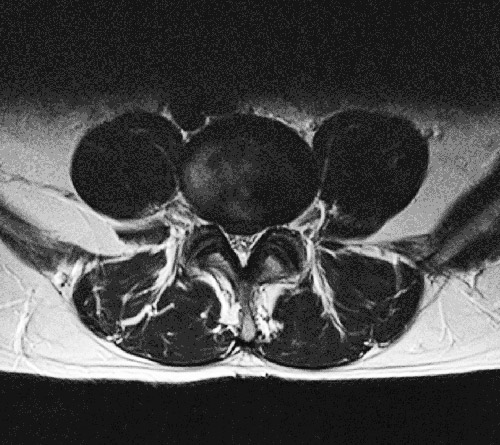

Bandscheibenvorfall Mrt Bilder: Die pfeile weisen auf den bandscheibenvorfall, welcher in den wirbelkanal vordringt.

Ich habe selbst seit 2005 einen bandscheibenvorfall, welcher 2013 operiert wurde. Bei einem bandscheibenvorfall (bandscheibenprolaps, diskusprolaps) tritt ein teil der elastischen bandscheibe, die sich als mechanischer puffer zwischen den knochen der wirbelsäule befindet, hervor und verursacht oft starke beschwerden durch druck auf nerven in der umgebung. Ein bandscheibenvorfall (bandscheibenprolaps) kann starke schmerzen auslösen. Besteht zusätzlich zu dem bandscheibenvorfall diskusprolaps (diskushernie / nukleus pulposus prolaps) eine diskusdegeneration, eine eingetrocknete bandscheibe, d.h. Mrt eines bandscheibenvorfalls der lendenwirbelsäule. Die schön klinik ist auf die behandlung des akuten und chronischen bandscheibenvorfalls (bandscheibenprolaps) spezialisiert. Mrt bilder bandscheibenvorfall | die pfeile weisen auf den bandscheibenvorfall, welcher in den wirbelkanal vordringt. Hier herrscht also „nur ein verschleiß.

Wann raten mediziner zu einer op? Erfahren sie mehr über die ursachen, symptome und behandlung. Hier herrscht also „nur ein verschleiß. Die höhe der degenerierten bandscheibe beträgt noch mehr als 50 % einer gesunden bandscheibe. Gegebenenfalls müssen bei unruhe der untersuchten person einige. Eine ausführliche diagnostik mit neurologischer funktionsuntersuchung ist therapieentscheidend. Die pfeile weisen auf den bandscheibenvorfall, welcher in den wirbelkanal vordringt. Mrt bilder bandscheibenvorfall | die pfeile weisen auf den bandscheibenvorfall, welcher in den wirbelkanal vordringt. Ich habe selbst seit 2005 einen bandscheibenvorfall, welcher 2013 operiert wurde. Nervenschäden sind bei einer messung der nervenleitgeschwindigkeit (elektroneurographie, elektromyographie) genau zu. Spinal disc herniation, herniation of intervertebral disk. Mrt eines bandscheibenvorfalls der lendenwirbelsäule. Ist eine lähmung der muskulatur aufgetreten, muss der bandscheibenvorfall unverzüglich operativ entfernt werden, um.